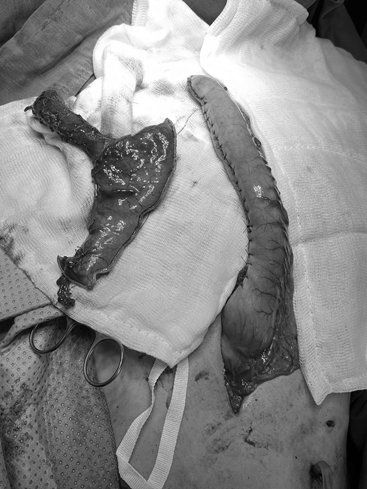

Sau nhiều lần nội soi kiểm tra và điều trị, các bác sĩ xác định: tổn thương thực quản của trường hợp anh T. không thể phục hồi bằng phương pháp nong thông thường. Do đó, một phương án đầy thách thức được các bác sĩ đưa ra, đó là: Phẫu thuật nội soi cắt thực quản và tạo hình lại bằng dạ dày.

Cuộc phẫu thuật được thực hiện bằng phương pháp nội soi đường bụng kết hợp mở cổ, nhằm cắt bỏ toàn bộ phần thực quản bị tổn thương và tạo hình một đoạn thực quản mới từ chính dạ dày của người bệnh. Ê-kíp phẫu thuật gồm Khoa Ngoại Tổng Quát, Gây Mê Hồi Sức,… đã phối hợp chặt chẽ, từng thao tác phải chính xác đến từng milimet. Sau nhiều giờ căng thẳng trong phòng mổ, phẫu thuật đã kết thúc thành công tốt đẹp.